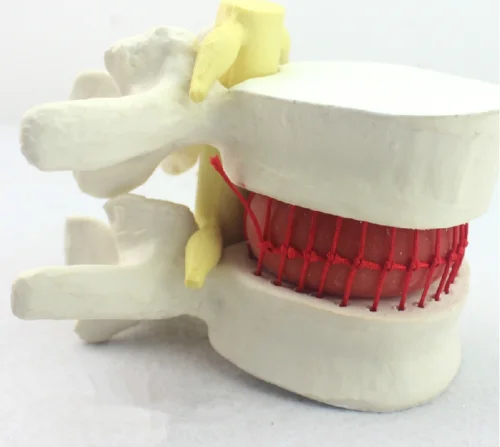

big sale! Lumbar Vertebra Slipped Disc Human Anatomical Medical Demonstration Model

aliexpress.com